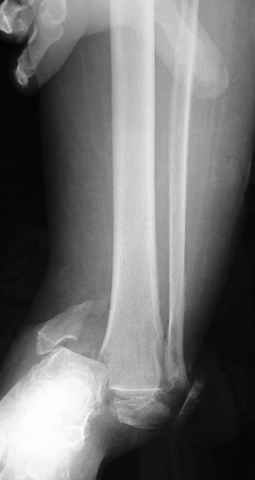

Pilon fracture:

ET> ЕЧ При подобных переломах фиксация малоберцовой кости обеспечивает

ET> низведение латерального тибиального фрагмента - появляется ориентир для

-Появляется ориентир и остов, на чем можно строить восстановление, почему сперва малоберцовую, впервые обьяснили и описали (Pylon type and Ankle fractures) в середине 50х Rienau и Gay.

Восстановливая длину и ротацию малоберцовой кости, затем относительно легче произвести реставрацию остальных элементов перелома дистального эпиметафиза болшеберцовой кости.

первую очередь, затем остальных элементов - стал классическим при лечении данной патолгии. Латеральная колонна (столб), дистальный

конец малоберцевой кости, к нему прикрепляется латеральный суставной фрагмент дистального эпиметафиза большеберцовой кости (как на снимке)

и таранная кость, которые при репозиции малоберцовой кости репонируются автоматически.